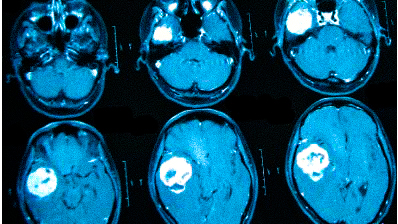

Выделяют несколько видов магнитно-резонансной томографии головы: нативную, усиленную контрастным препаратом и сканирование в ангиорежиме. К каждому исследованию есть свои показания, поэтому ответить на вопрос: “Какую МРТ делать при головной боли?” — не всегда возможно. Врач выбирает нужный тип диагностики, опираясь на клиническую картину. В оценке опухолевых новообразований и для определения стадийности (в том числе — метастатического распространения) используют МРТ с контрастированием. Введение препаратов на основе хелатов гадолиния позволяет рассмотреть даже небольшие опухоли в труднодоступных местах, поэтому магнитное сканирование с усилением с успехом применяют, если прочие способы визуализации показали неоднозначные результаты. При подозрении на сосудистое заболевание головного мозга оптимальным выбором будет проведение сканирования в ангиорежиме.

опухолевые процессы доброкачественного или злокачественного генеза;

Онкологи считают, что при нарастающих головных болях с прочими необъяснимыми симптомами (обмороками, ухудшением памяти, выпадением полей зрения, давлением на глазные яблоки и др.) в первую очередь следует исключить опухолевую патологию